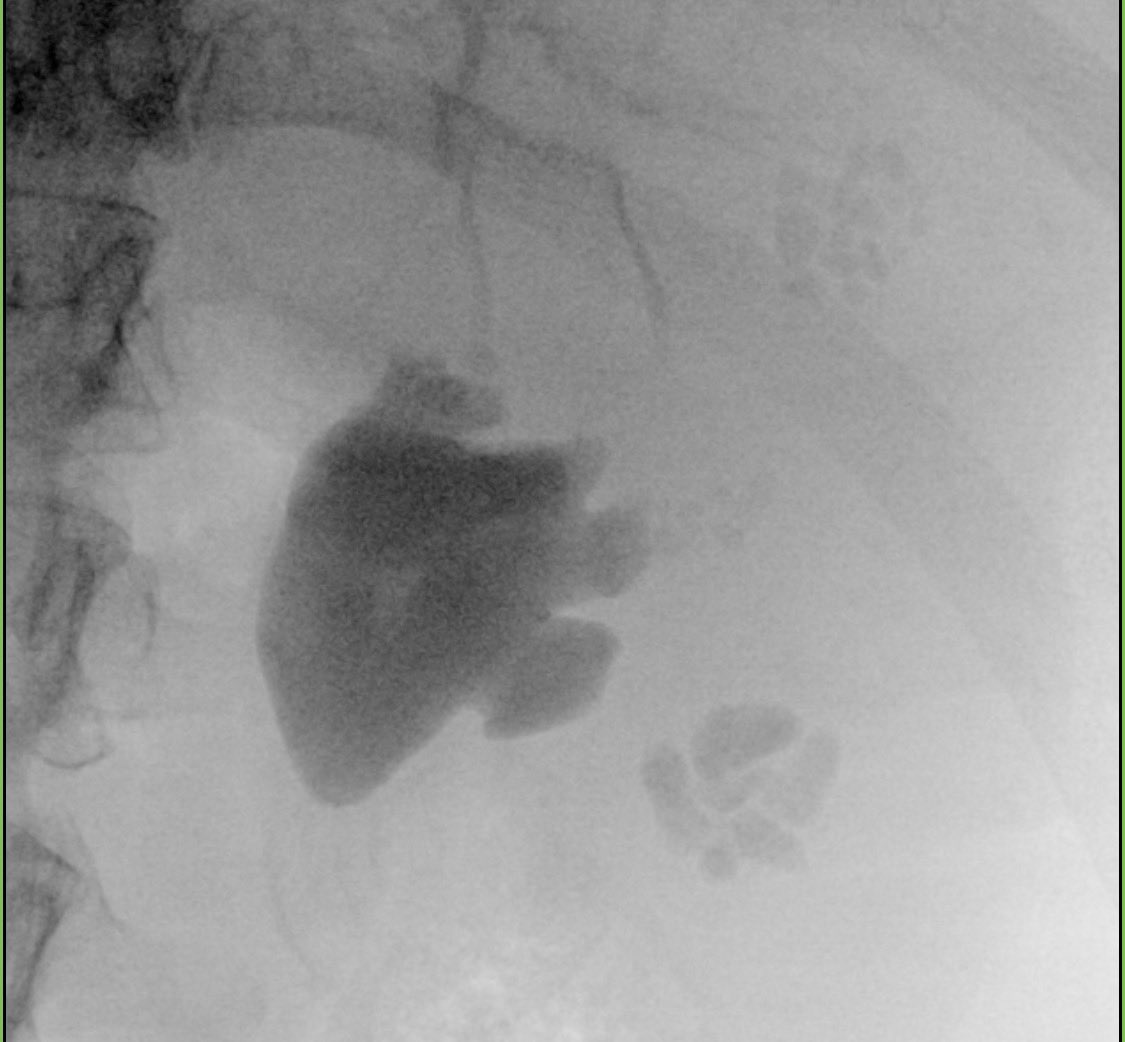

MOSES 2.0 vs QUANTA 150: first single-center direct comparison of modern pulse-modulated holmium systems for enucleation. Both platforms achieve excellent safety profiles, but QUANTA 150 demonstrated marginally greater procedural efficiency in this analysis. Critical data for equipment procurement decisions - the future of holmium laser lies in pulse modulation optimisation, not just power increases. For high-volume centres investing in laser upgrades, this head-to-head comparison provides the evidence base we have been missing. Technology advancement should serve technique refinement, not replace surgical fundamentals. pubmed.ncbi.nlm.nih.gov/41810687/